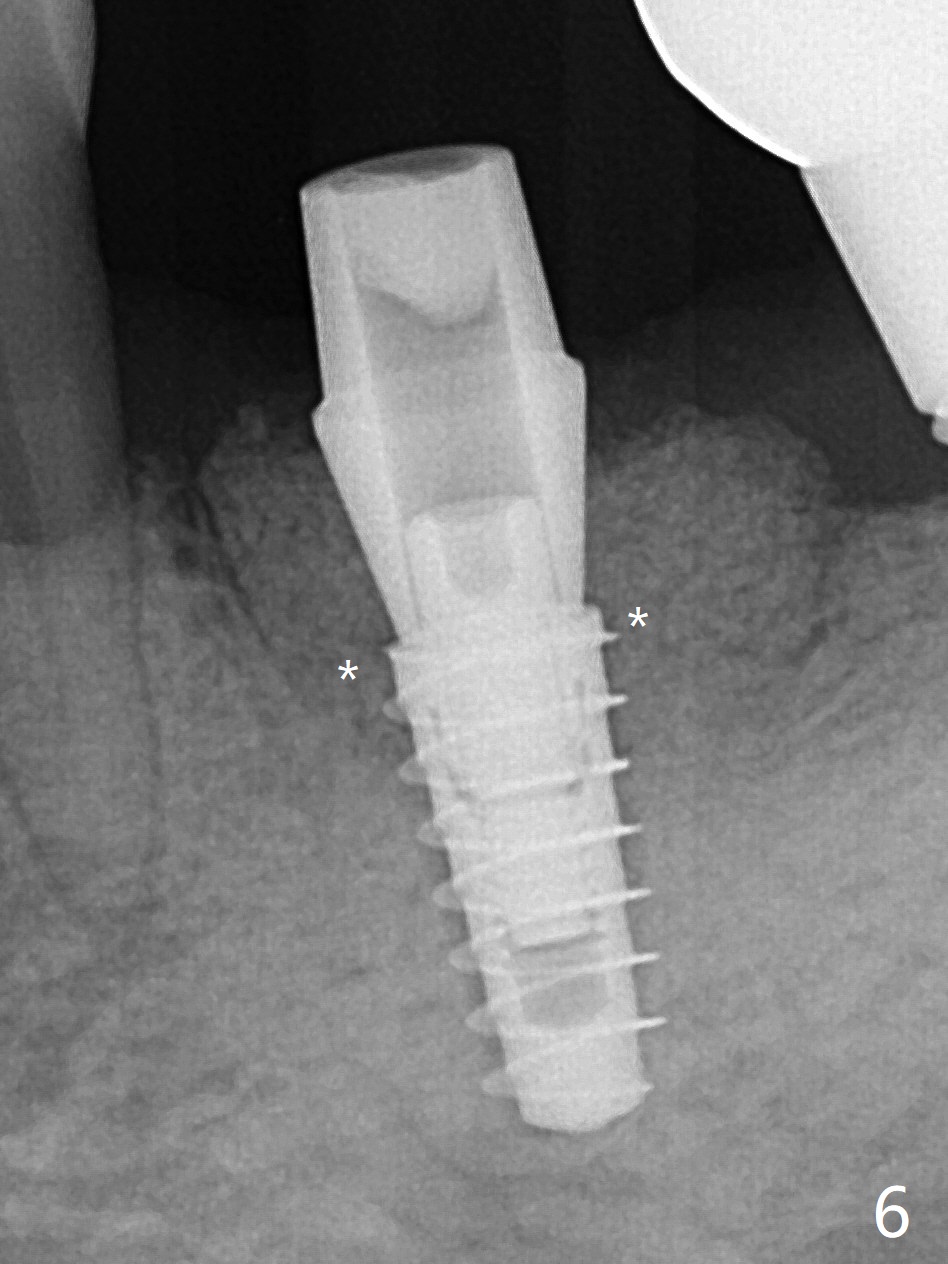

The 59-year-old man has so severe pain associated with #19 that he returns for extraction 2 days prior to guide arrival (Fig.1,2).拔牙后两天瘘道消失,牙槽窝口关闭(图三)。导板钻洞(4x7.3毫米)后,置入4x11毫米软组织水平植体,好像太短(图四),离神经(红虚线)3.5毫米。使用3.5x8.5毫米钻头后,植入4.5x9毫米骨水平植体,多次倒退,扭力35Ncm;马上安置基台(图五),然后粘性骨粉(图六:*)。